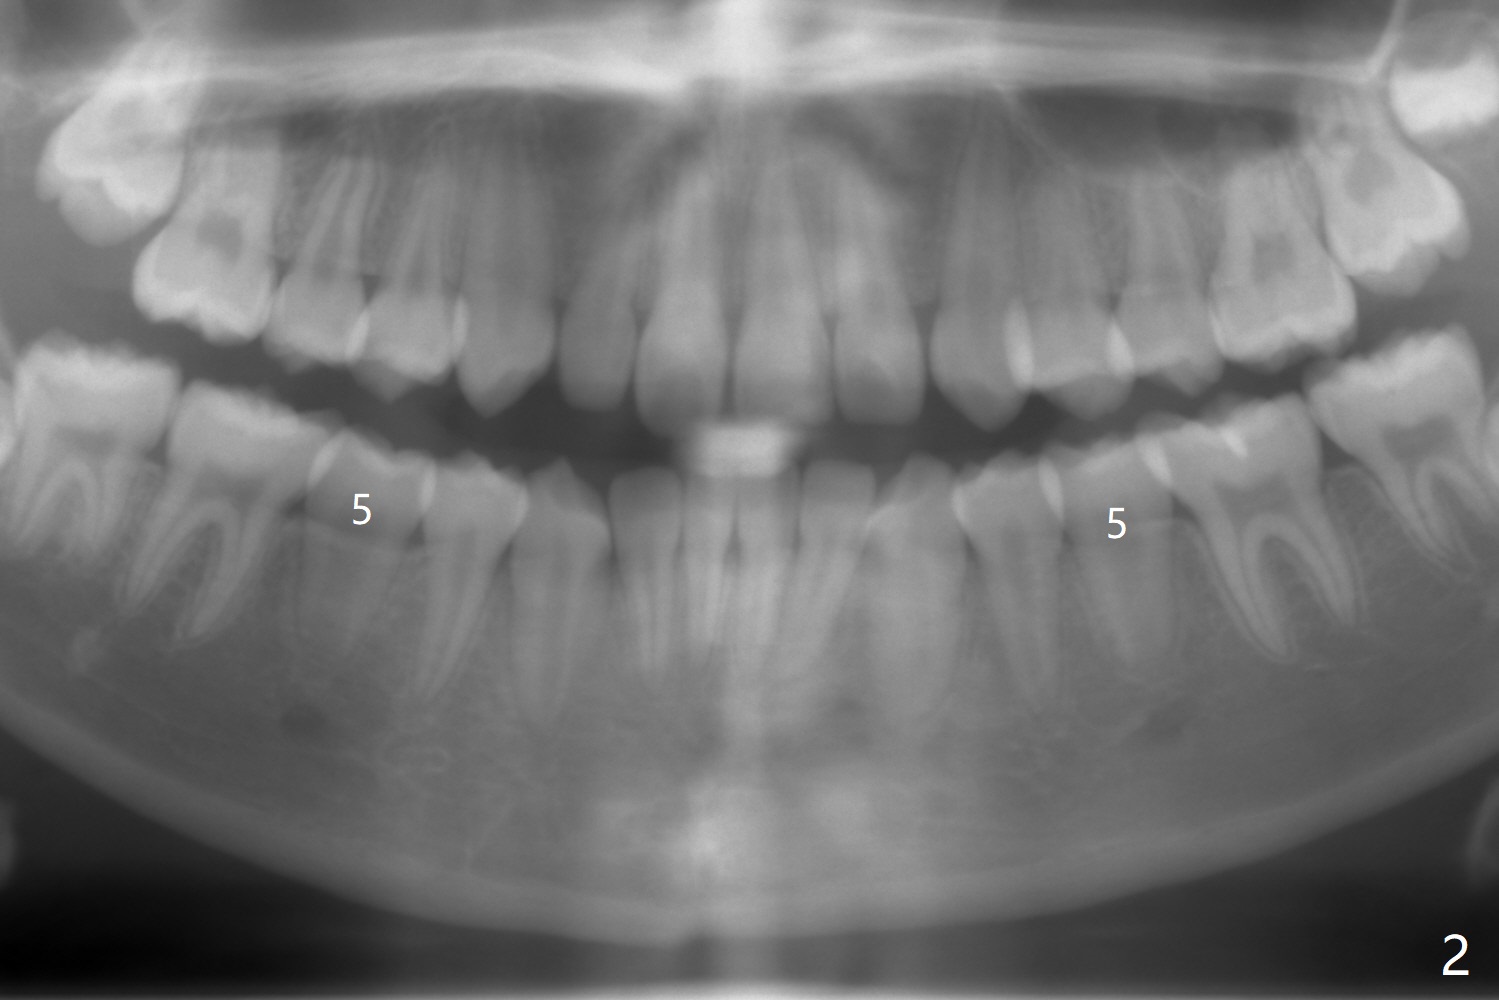

The lower right 2nd bicuspid of a 10-year-old woman seems to rotate before eruption (Fig.1: 5) and remains so when it erupts (Fig.2, at the age of 12).

LR5 rotation appears to be associated with poor interdigitation on the right side (Fig.3), as compared to the left (Fig.4). * in Fig.3-6 indicates height of contour of a lower bicuspid, where a bracket should be placed.